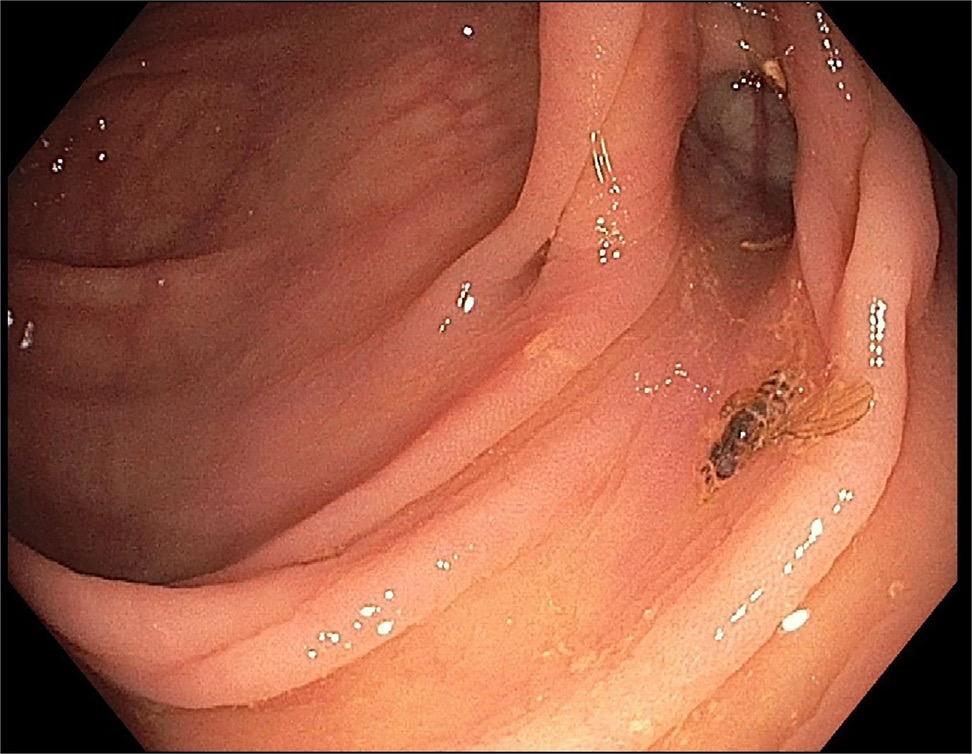

Unusual to “Bee” in the Colon: A Rare Finding on Screening Colonoscopy by Yousaf and Bechtold